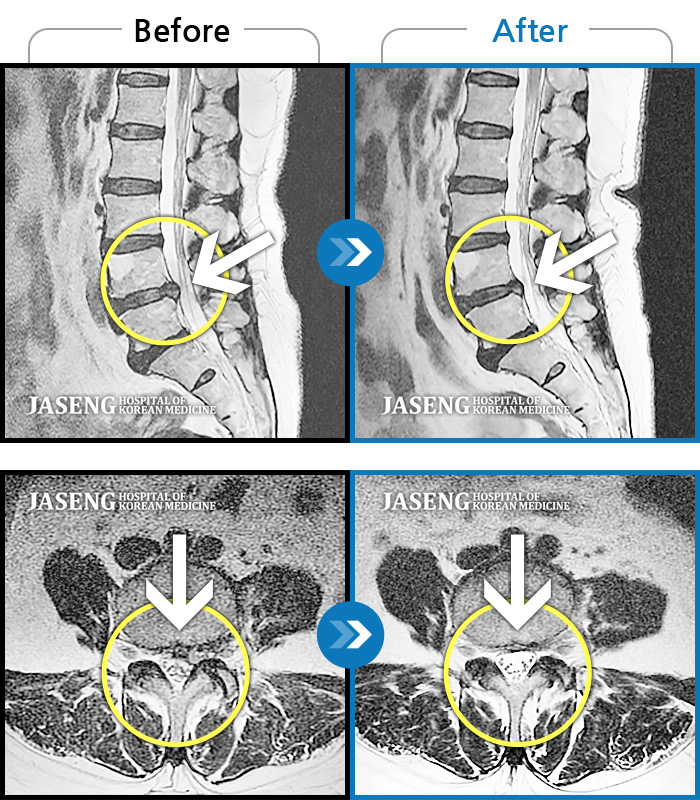

MRI 치료사례

앉아있다가 일어날 때 허리가 펴지지 않으면서 끊어질듯이 아파요.